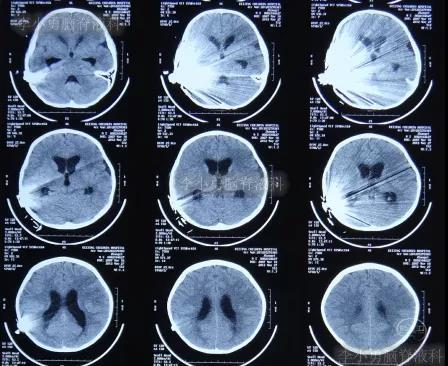

在利奈唑胺、头孢吡肟、利福平等药物抗炎治疗2周后,发热症状逐渐得到控制,意识也开始转清醒,但患儿自己示意有头痛症状;因腰穿未能抽出脑脊液,所以给予甘露醇处理,之后头痛可有缓解。在住院11天时即2012年5月27日(图-4)和住院14天时即2012年6月1日(图-5),分别进行过脑CT的检查,显示脑室有逐渐扩大的表现,但因为病情有所缓解,所以给以继续密切观察的处理。

图-4:2012年5月27日脑CT脑室稍扩大

图-5:2012年6月1日脑CT脑室稍扩大

但是在住院第19天即在2012年6月6日时(注:即在人工耳蜗植入术颅内感染并发症21天时),患儿出现了左眼闭合和右侧肢体瘫痪即交叉性偏瘫,以及进食无力和不能交流的病情加重的表现,立即脑CT检查发现了脑积水的表现(图-6)。

图-6:2012年6月6日脑CT脑室扩大显著

入院当天脑CT检查发现,脑积水又有加重表现(图-8)。

图-8:2012年6月7日脑CT脑积水加重

入院治疗18天即2012年6月25日,查脑CT示脑室有缩小(图-10)。

图-10:2012年6月25日脑CT

入院治疗55天即2012年8月1日,进行了脑室腹腔分流术,术后当天查脑CT示未见异常(图-11)。

图-11:2012年8月1日脑CT